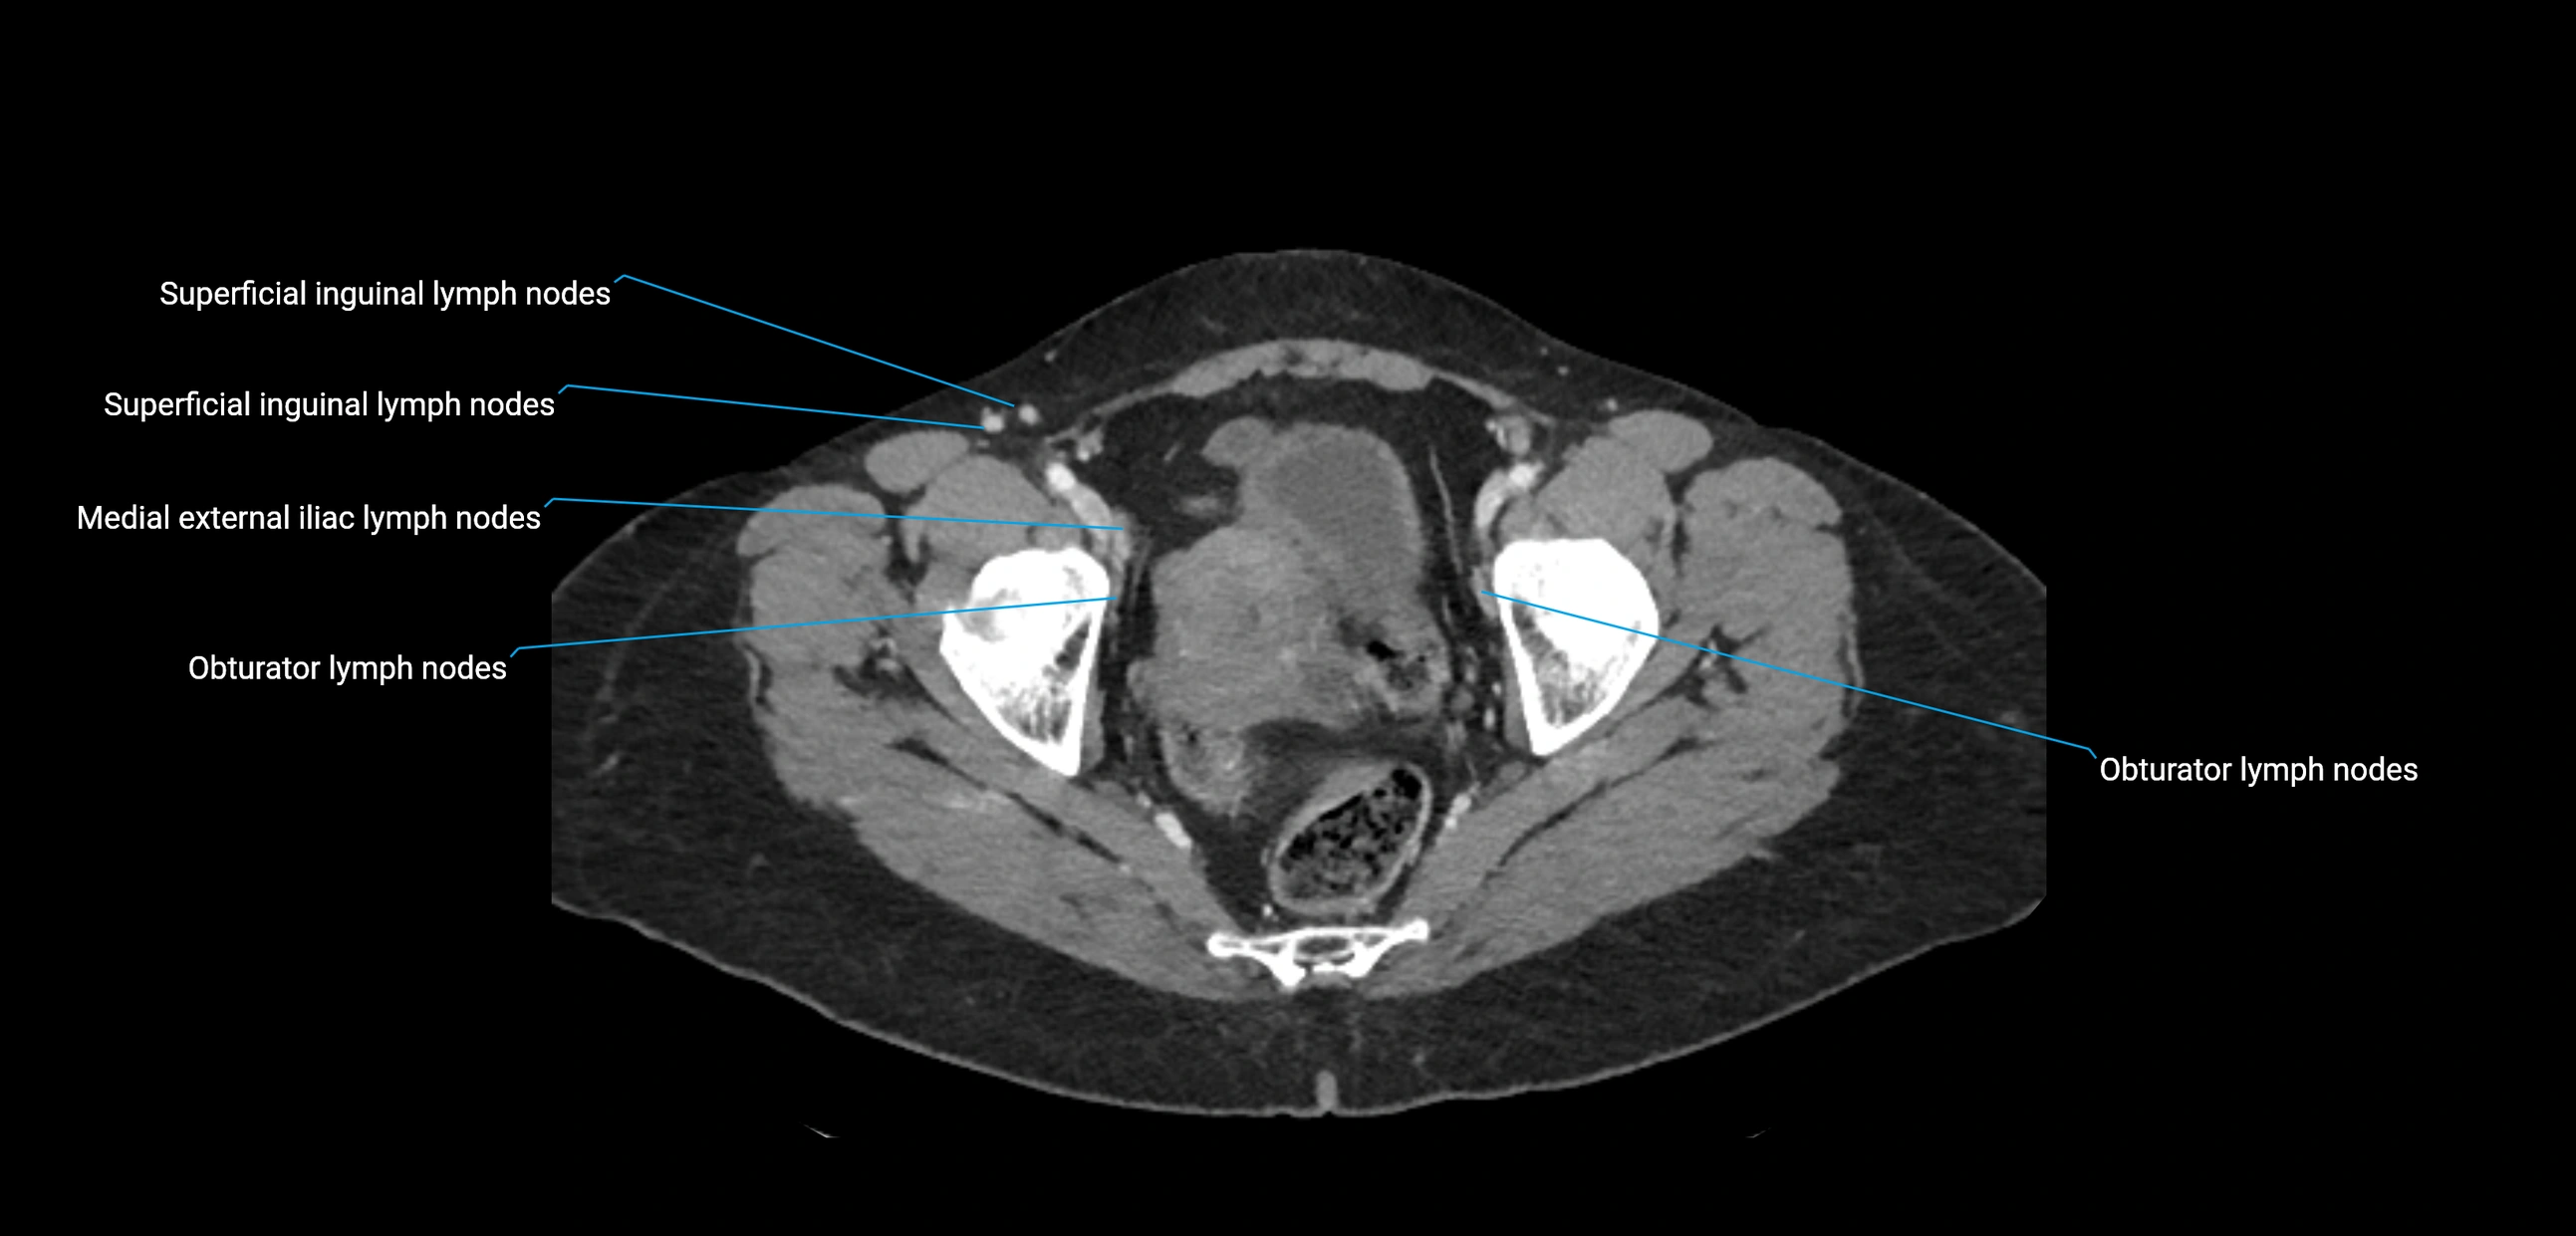

CT Appearance

CT Pre-Contrast:

• Nodes appear as soft-tissue density nodules adjacent to the aorta and IVC

CT Post-Contrast:

• Normal nodes enhance homogeneously

• Malignant nodes may show heterogeneous enhancement, central necrosis, or conglomerate formation

• Size >1 cm short axis is suspicious, though morphology and distribution are equally important

CT image

image